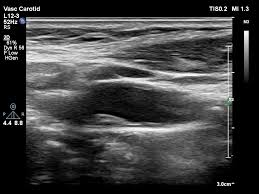

경동맥 초음파 검사는 고주파 초음파를 사용하여 목의 경동맥 혈관을 영상으로 확인하는 검사입니다. 혈관 내벽 두께, 혈류 흐름, 좁아진 정도 등을 실시간으로 볼 수 있으며, 조영제나 방사선 노출이 없어 안전합니다. 검사 시간은 약 20~30분 정도 소요됩니다.

2) 죽상동맥경화증

플라크(지방 덩어리)가 혈관 벽에 형성되어 혈류를 방해합니다. 증상이 없더라도 뇌경색 위험을 높이는 원인이 됩니다.